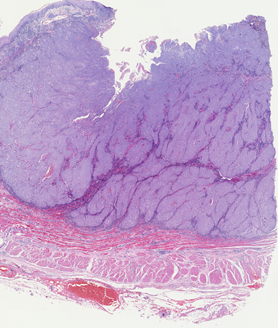

For almost two decades, we have provided prepared slides suitable for various biomedical courses. These glass slides contain sectioned, mounted, or smeared tissues stained with different methods.

They can be used to study histology, pathology, oral histology, oral pathology, embryology, microbiology, parasitology, and hematology.

Click the following categories to view example photos taken from these prepared slides.

The representative photos shown in each category are examples taken under the light microscope. They may not be the same ones as those available for your need. Complete lists of prepared slides for each course can be downloaded for further consideration.